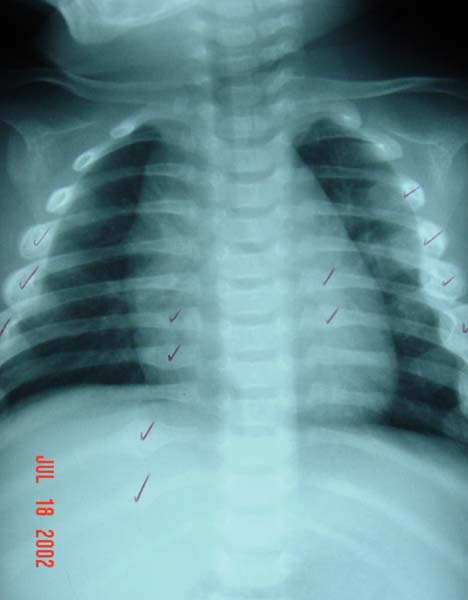

Left: Inflicted rib fractures in a 9-month-old child. Note the callus formation. Right: The same child 2 weeks later (in protective custody). Note the two new calluses.

This emphasizes the need for a repeat skeletal survey 2 weeks after the first.

(Photos courtesy of Children’s Hospital Boston Child Protection Team.)